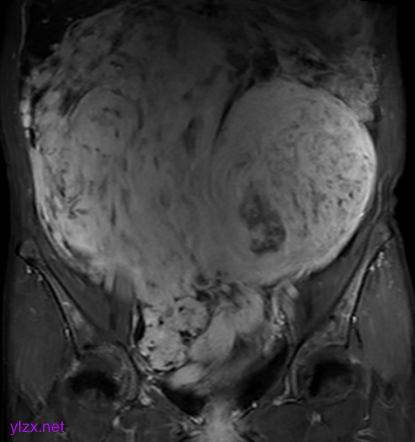

MRI检查:

子宫右侧巨大实性占位,大小约260×110×91mm,与子宫分界不清,T1WI呈稍低信号,T2WI呈不均匀稍高信号,呈束状、旋涡状改变(图1),病变内部分可见囊变,肿瘤内部及表面多发流空血管影(图2);DWI上病变呈略高信号,ADC图呈略低信号,ADC值为1.633×10-3 mm2 /s;增强扫描呈明显强化(图3),内部见条片状低信号。影像学考虑子宫右侧恶性肿瘤。

图1

图2

图3

子宫PEComa影像学表现各异,其MRI表现具有一定的特征,肿瘤T2WI信号稍高,呈束状排列,富血供,可伴有变性、坏死,肿瘤内部及表面可见多发流空血管影。